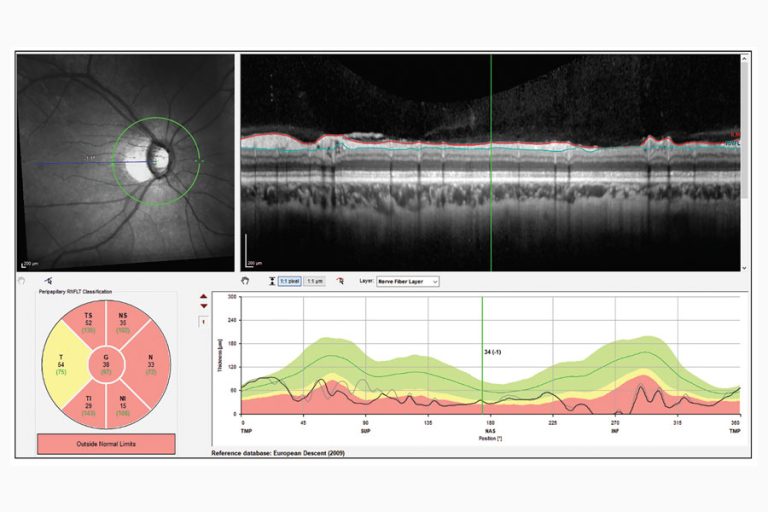

Figura 3. Artefacto de segmentación de miopía alta en paciente con una cavidad de esquisis en la capa de fibras nerviosas. Estas cavidades hacen que la RNFL parezca normal en espesor.

“Los quistes, o cavidades de esquisis, en la capa de fibras nerviosas en pacientes miopes pueden hacer con que la capa de fibras nerviosas se vea normal en espesor”, continúa el Dr. Asrani (Figura 3). “Además, la uveítis causa edema en la capa de fibras nerviosas. Por lo tanto, siempre que haya un diagnóstico coexistente de uveítis, la OCT debe usarse con extrema precaución porque lo que podría aparecer como una capa de fibra nerviosa normal puede ser artificialmente normal, ya que no está compuesta de tejido sino de líquido. Por lo tanto, los resultados de la OCT tienen que correlacionarse con el campo visual para pacientes con uveítis.